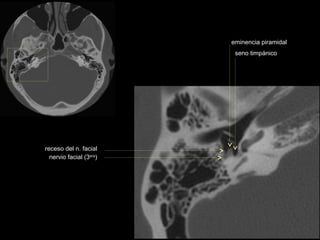

CATEDRA DE RADIOLOGIA U.N.L.P.   Hueso temporal normal              Edición 2002

ap.pterigoides                                             vómer

cóndilo del

clivus

maxilar inferior

mastoides

sutura

occipito-temporal

protuberancia

occipital interna

seno maxilar

conducto

carotídeo

auditivo externo

occipital externa

trompa de Eustaquio

conducto auditivo externo

celdillas mastoideas

eminencia piramidal

seno timpánico

receso del n. facial

nervio facial (3era)